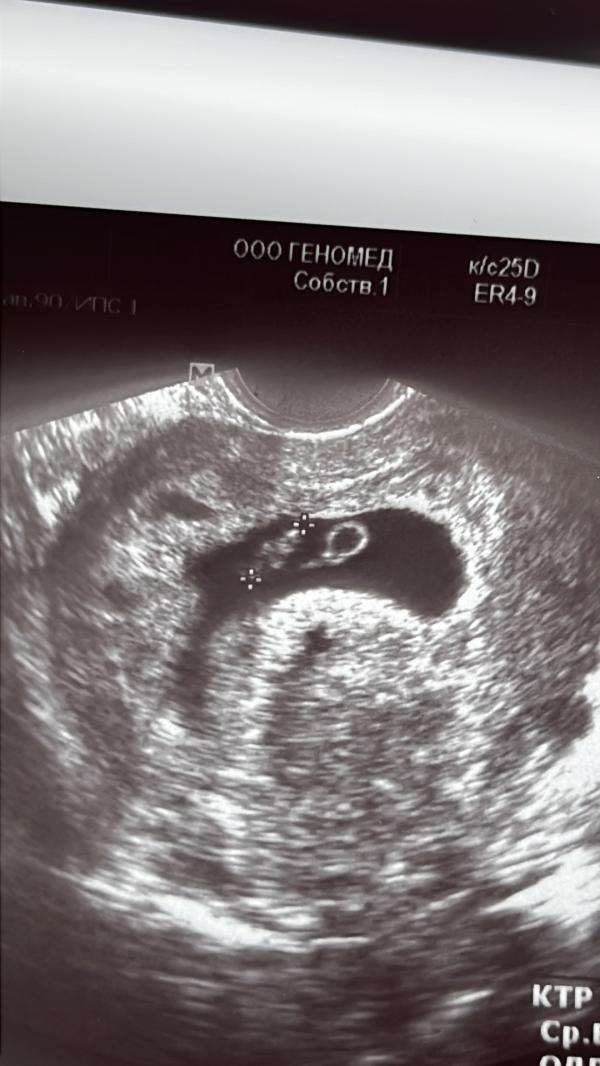

Первое УЗИ при беременности: результаты и постановка на учёт

Сходила на узи ☺️ малыш уже ктр 0,94 . Чсс 156 . 7,2 все по сроку . В среду вставать на учет